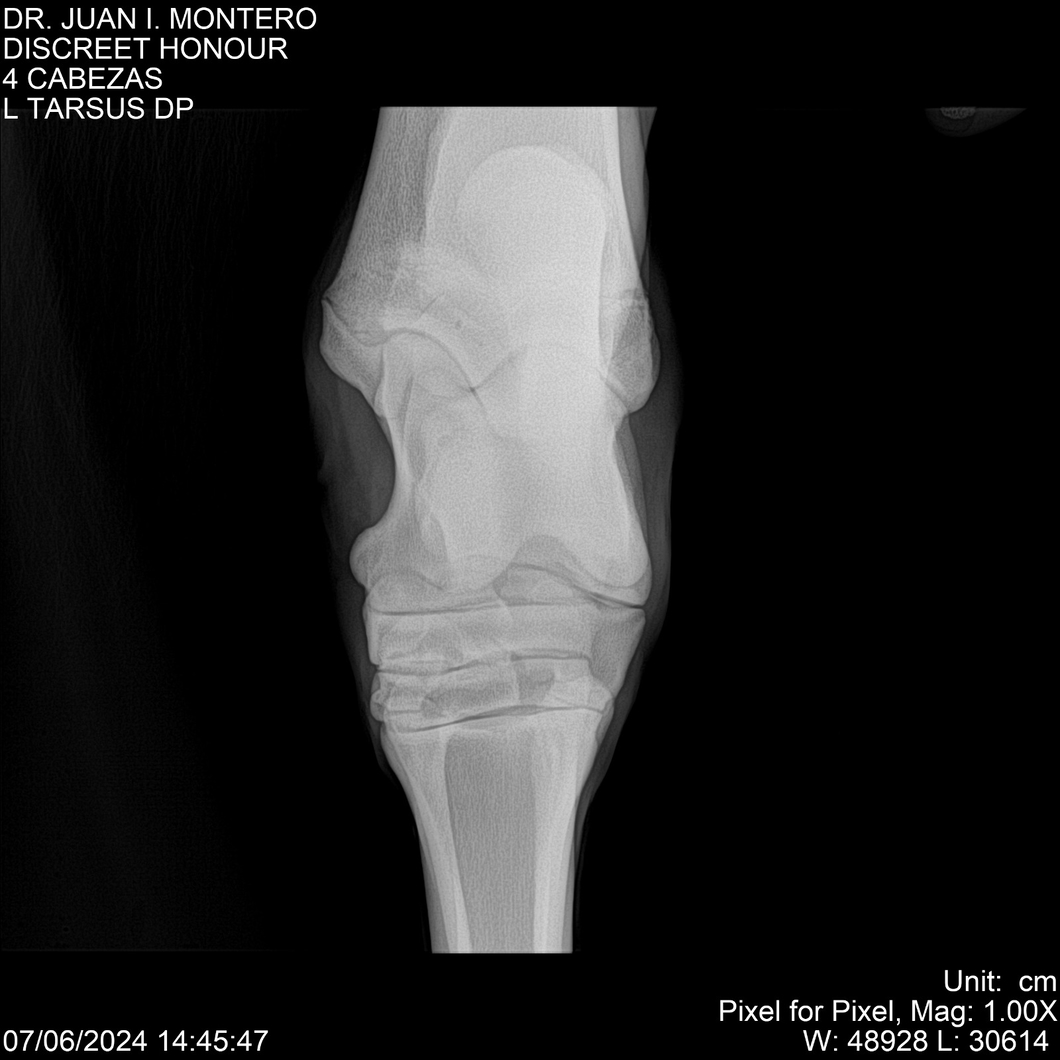

LOTE 6, DISCREET HONOUR 🔥 🔥 🔥 Lote Anterior Volver al remate Lote Siguiente Ficha Contacto Montevideo - Ficha del Lote Identificador: #281093 Categoría: Yeguarizos Montevideo - 82 Visualizaciones ClicData Contacto Empresa: Abelenda N. R., Walter Hugo Nombre*: Teléfono* : E-mail* : Mensaje Enviar Registrese gratis Este contenido Exclusivo está disponible sólo para usuarios registrados Ingresar